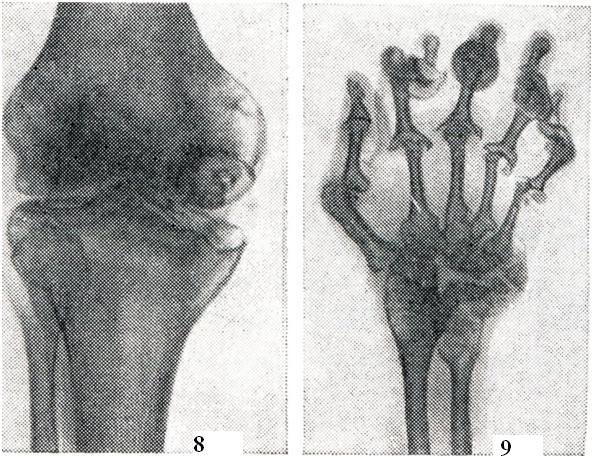

Рентгенологическая симптоматика артрита многообразна и включает следующие признаки: остеопороз во всех его разновидностях; иногда расширение суставной щели или чаще ее сужение (тотальное или частичное) в связи с наличием деструктивных изменений в костно-хрящевых элементах сустава; краевые костные дефекты, так наз. узуры, на суставных поверхностях как следствие деструктивных процессов; наличие очагов деструкции в околосуставных участках костей; образование секвестров, нередко наблюдаемое при специфических, в частности туберкулезных, артритов (рис. 8); периостальные наложения в области метафизов длинных трубчатых костей, а также реактивный остеосклероз; изменения рельефа суставных поверхностей костей и краевые костные разрастания на костях, образующих сустав; вывихи и подвывихи, возникающие в результате деформации суставов при некоторых формах артрита (рис. 9).

Рис. 8.

Специфический (туберкулезный) гонит. Крупный подхрящевой секвестр в медиальном мыщелке бедренной кости. Краевая деструкция мыщелков бедра и большеберцовой кости в области прикрепления суставной сумки. Сужение суставной щели. Остеопороз (рентгенограмма).